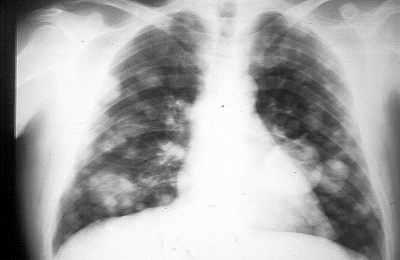

Метастазы в легких на рентгене могут быть определены и в прямой, и в боковой проекциях. Рентгеновский снимок способен показать специфические и неспецифические виды очагов с метастазами. Для некоторых опухолей характерен вид единичных очагов, характеризующихся средней интенсивностью. Метастазы имеют вид дорожек, а их контуры подрытые.

Метастатические поражения присутствуют у каждого третьего пациента, у которого диагностирован рак.

На рентгенограмме злокачественного образования в легких можно увидеть такие признаки, как наличие узловых образований с нечеткими границами, увеличение лимфатических узлов, а также изменения в структуре легочной ткани, такие как уплотнения или затемнения. Эти изменения могут указывать на наличие опухоли.